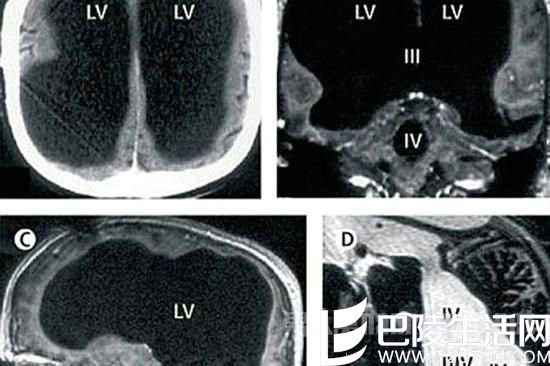

医生指出,萎缩的这些部分是控制人类运动、感觉、语言、视觉、听觉、情感及认知能力的部分。在对这名男子的病史进行详细调查后发现,原来他童年时患有后天脑积水症。

但在他14岁时,经历了分流术,随后的30年,这名男子和家人都以为完全康复了。但其实他的大脑还是在病变,最终,脑内的积水损坏了脑组织。

导致其大脑50%至75%的部分都消失了。那这名男子又是如何存活下来且一切生理功能都正常的呢?在经过了8年的研究后,科学家认为,人类的大脑其实有自我重组功能。